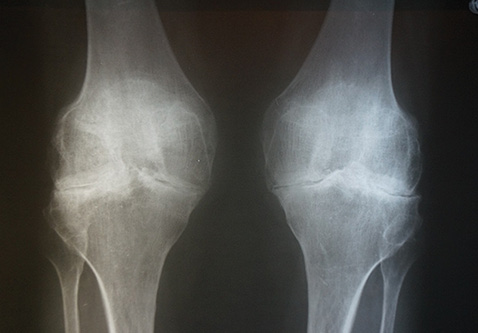

У пацієнта на рентгенограмі визначено крайове загострення замикальних пластин, міжвиросткових піднесень великогомілкових кісток, що відповідає І–ІІ стадії рентгенологічних змін за Kellgren (рис. 8).

Рис. 8. Рентгенологічне дослідження суглобів пацієнта М.

Таким чином, отриманий прогноз на основі значень метаболічних показників за допомогою математичної моделі правильний.

У пацієнтки на рентгенограмі виявлено склероз, масивні крайові кісткові розростання замикальних пластин великогомілкових костей, рентгенівські суглобові щілини різко звужені, що відповідає ІІІ стадії рентгенологічних змін за Kellgren (рис. 9).

Рис. 9. Рентгенологічне дослідження суглобів пацієнтки Б.

Таким чином, отриманий прогноз на основі значень метаболічних показників за допомогою математичної моделі є правильним і в цьому випадку.